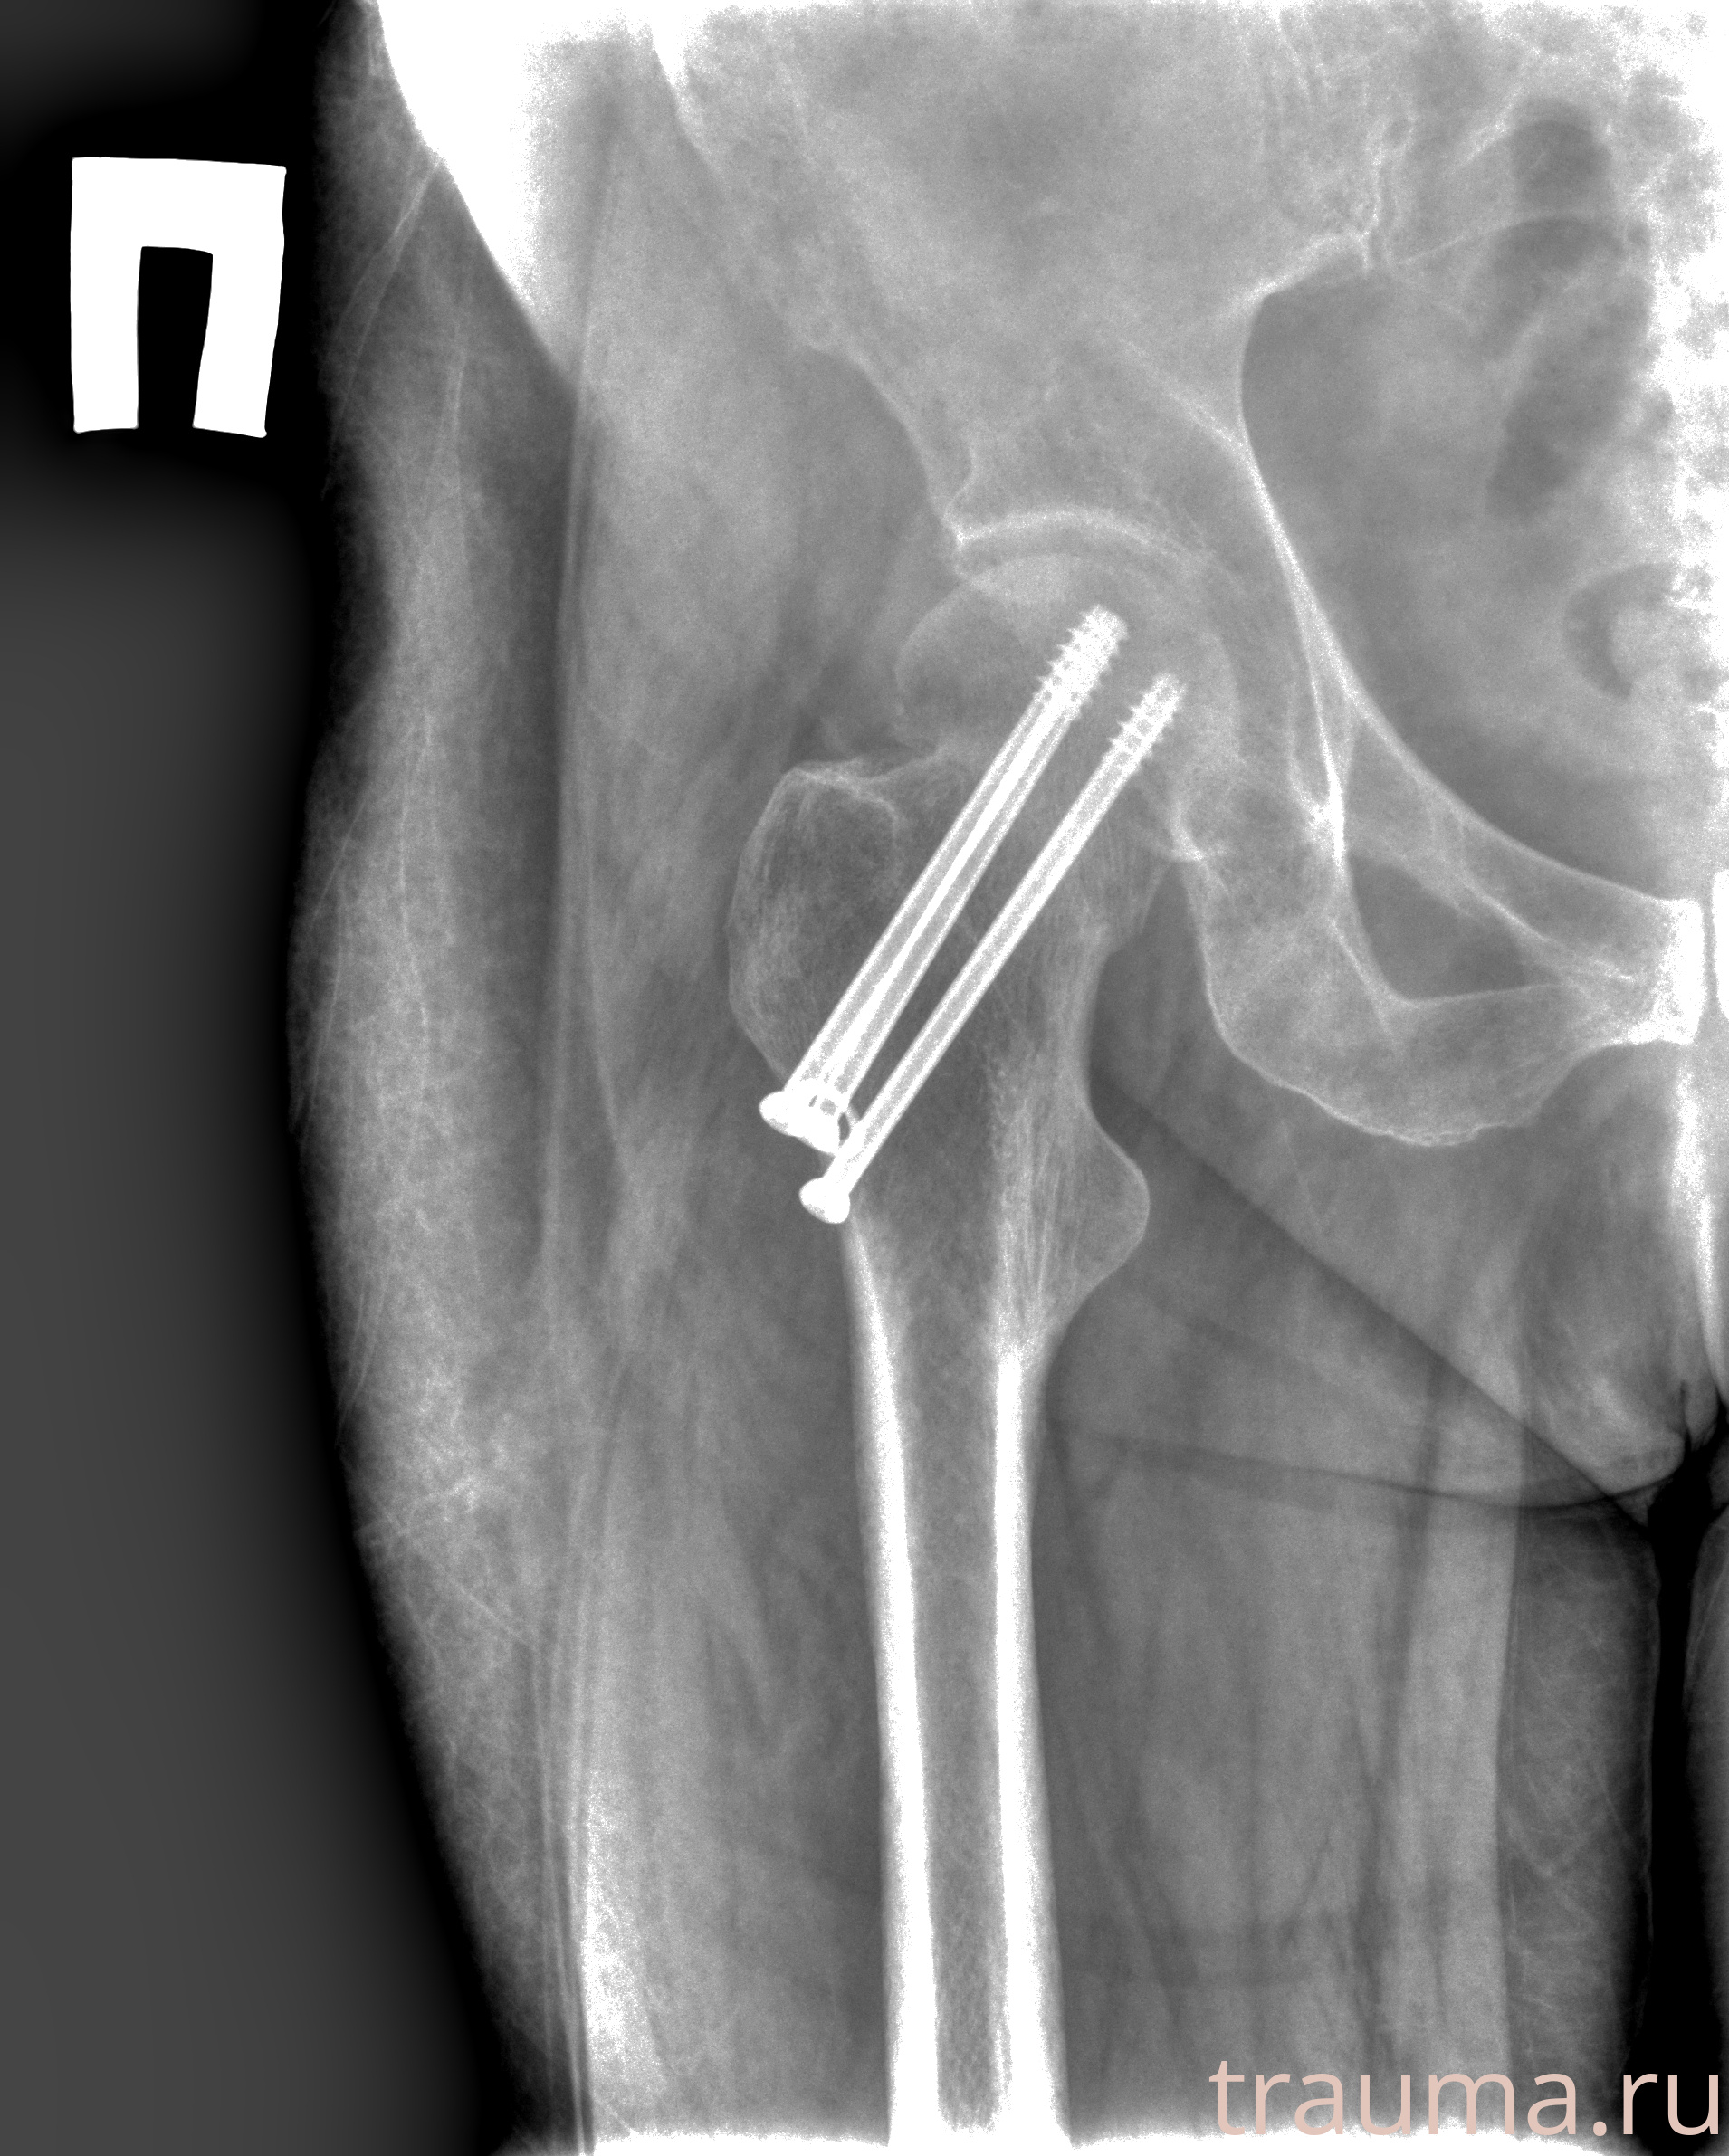

Рентгенограммы

Рентген на дому: по вашему адресу приезжает врач-рентгенолог, травматолог-ортопед с мобильным рентгеновским аппаратом, проводит диагностику травмы или заболевания, делает необходимые рентгенограммы, дает рекомендации по дальнейшему лечению. Получить качественные снимки в домашних условиях возможно благодаря уникальной методике, разработанной МосРентген Центром для института  Склифосовского